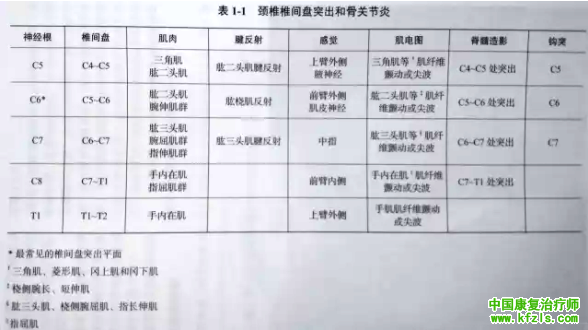

表1-1 归纳了颈椎各平面的神经功能检査方法, 同时也总结了其在颈髓病变尤其是颈椎间盘突出症中的临床应用。

2.肌电图:该技术能准确地检测运动电位。神经损伤2周后即可检测到静息肌肉的不自主放电反应(肌纤维颤动电位和正尖波)。

肌电图还可检测出肌肉的去神经化表现,这可由椎间盘突出、神经根撕裂伤或者脊髓损伤导致,亦可由神经丛或者外周神经损伤引起。在临床检査时,对判断神经节段(肌节)的代表肌肉应进行完整的评估(详见表1-1 )。